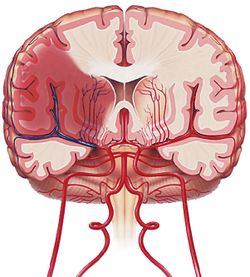

السكتات الدماغية الناتجة من نقص التروية ischemic stroke

السكتة الدماغية بنقص التروية. «انسداد في أحد الشرايين الدماغية يؤدي إلى احتشاء دماغي».

يقدر هذا النوع من السكتات بنحو 80 ـ 85% من الأمراض الوعائية الدماغية. وفيه يحدث نقص أو انقطاع في وصول التروية الدموية إلى جزء من الدماغ بإحدى الآليات الرئيسية الآتية:

ـ انسداد في الوعاء الدموي نتيجة دخول صمة embolus (أو خثرة) جاءت من مصدر آخر (من القلب مثلاً).

ـ تضيق في الشريان نتيجة إصابة في جداره مثل التصلب العصيدي (atherosclerosis).

ـ نقص في قدرة القلب على ضخ الدم إلى الدماغ (كما يحدث في احتشاء العضلة القلبية الواسع أو عقب توقف القلب).

ـ أمراض في خواص الدم ووظائفه (منها فرط اللزوجة وزيادة قابلية التخثر).